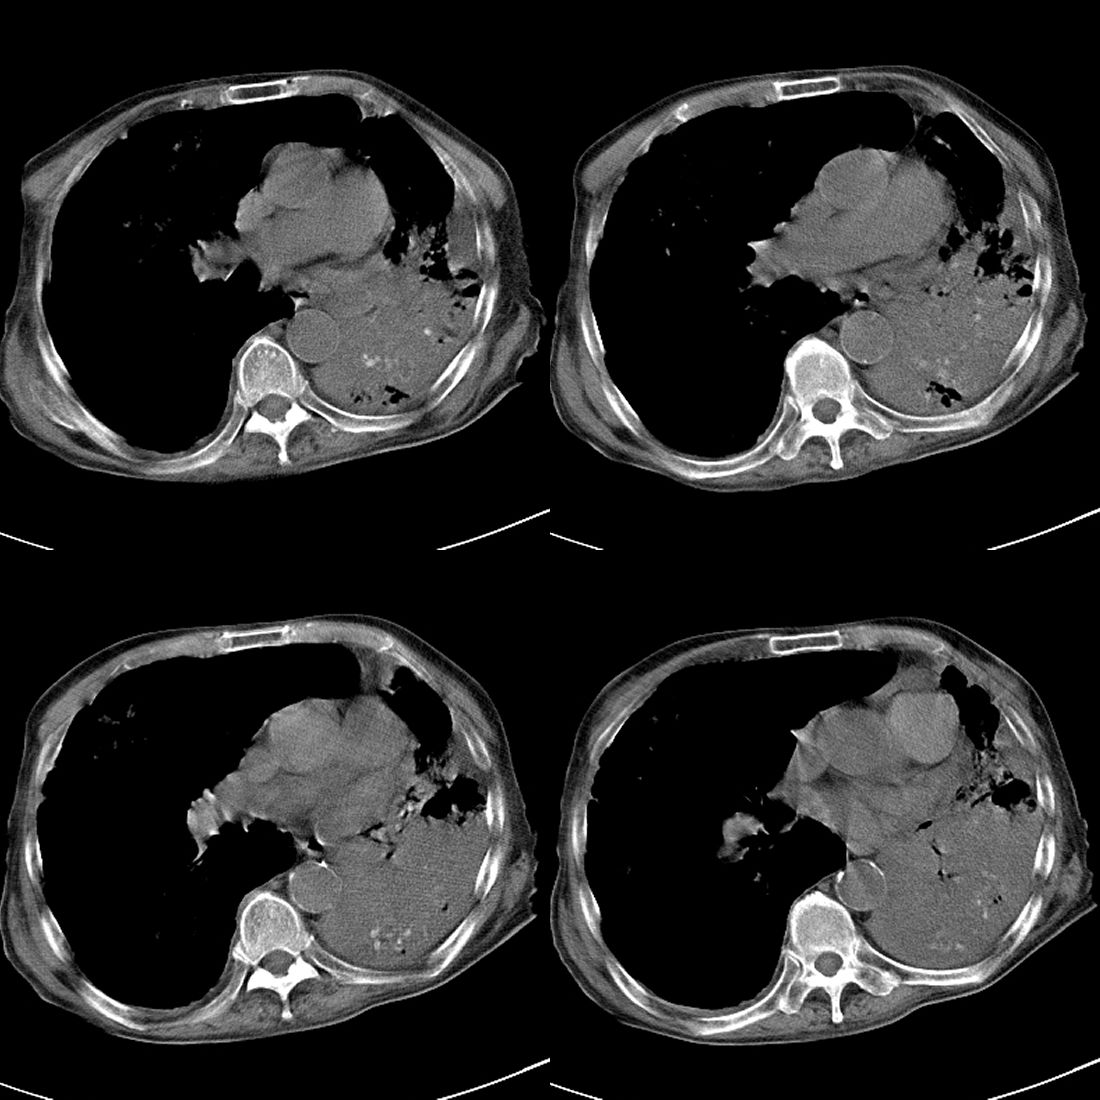

以下是引用liuyue在2008-11-30 6:01:00的发言:[br]双肺继发性肺结核;左侧包裹性积液;建议增强化或支气管镜检查除外左肺占位性病变.

以下是引用吴承学在2008-11-30 8:02:00的发言:[br]双肺继发性肺结核;左侧包裹性积液;建议增强化或支气管镜检查除外左肺占位性病变.[br]